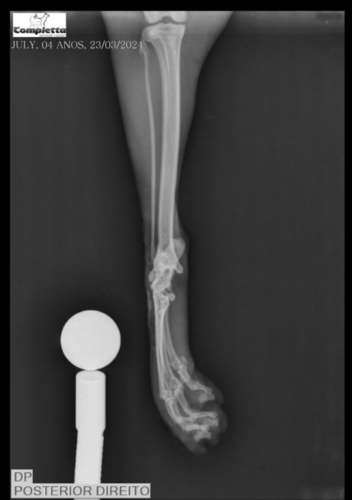

Minha gata foi atropelada ontem (22/03/24) e não prestaram socorro e as patas traseiras dela foram comprometidas (uma totalmente virada ao contrário) e será necessário realizar uma cirurgia para colocar a pata no lugar pois ainda a chance de salvar o membro, porém a cada dia que demoramos para pagar a cirurgia é um dia a menos que ela tem de conseguir manter as patas traseiras sem a necessidade de amputar.